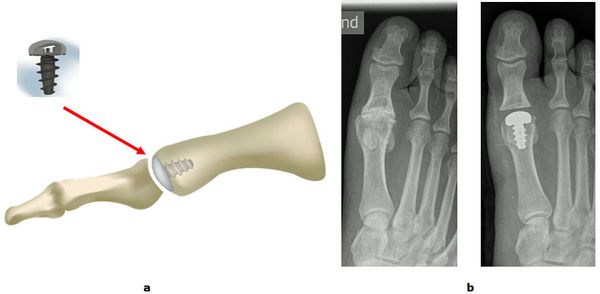

Die rekonstruktive Versorgung mit einer Endoprothese ermöglicht dem Patienten im Vergleich zur Fusion eine schnellere Mobilisation mit Erhalt des Abrollvorgangs. Eine Vollbelastung ist bereits direkt nach dem operativen Eingriff erlaubt. Dennoch eignet sich nicht jedes Gelenk für eine Endoprothese. In Fällen von erheblichen Knochenverformungen oder spezifischen Knochenerkrankungen (Infektion, Osteonekrose) ist weiterhin die Versteifung die Therapie der Wahl. Die Entscheidung welches Verfahren am sinnvollsten ist hängt auch von dem Bewegungsradius im Großzehengrundgelenk und den Längenverhältnissen der Zehen ab.

Abb.7: Implantation einer Endoprothese Typ Hemi CAP im Großzehengrundgelenk.

a Schema und Modell

b Röntgenbilder Vor und nach der Operation